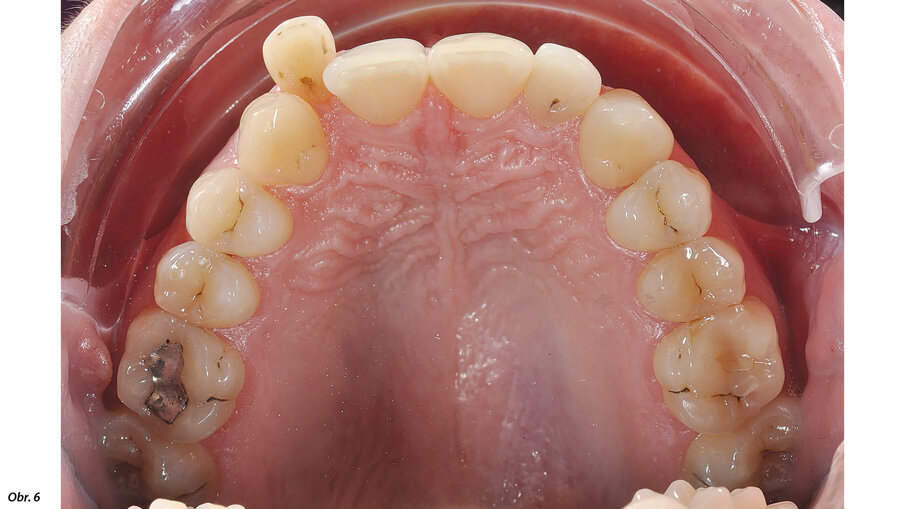

Vyšetřením jsme zjistili výrazný nedostatek místa v horní i dolní frontě. Zub 12, s meziodistální šířkou 6,25 mm, byl eruptován vestibulárně zcela mimo zubní řadu se současným posunem horní středové linie doprava. Mezera mezi zuby 11 a 13 činila 1,5 mm. Nedostatek místa v dolním zubním oblouku činil 2,6 mm resp. 2,85 mm ve dvou dolních kvadrantech. V transverzálním rozměru byl oproti normě menší jak anteriorně, tak i posteriorně. Oproti tomu skus laterálně a v místě špičáků byl normální – zde jsme diagnostikovali I. třídu podle Anglea. Hloubka skusu byla 0,5 mm s tendencí k otevřenému skusu. Incizální schůdek byl 0 mm se skusem hrana na hranu u zubů 11/41 a 21/31/41. Podle Boltnových indexů byl přítomen nepoměr v šířce zubů s přebytkem „zubního materiálu“ v dolní čelisti (obr. 3–5). Při skeletální diagnostice jsme nalezli disharmonii ve velikosti čelistí s retrognátní horní čelistí a ortognátní mandibulou – III. skeletální třída s úhlem ANB -2,3° a hodnotou WITS o velikosti -3,9 mm. U vertikální analýzy byl zřejmý mírně horizontální typ růstu s hodnotou SpP/MeGo 23° a poměrem SGo/NMe 71 % na základě anteriorní inklinace horní čelisti. Interincizální úhel byl lehce zvětšený, což bylo dáno mírnou protruzí horních řezáků spolu s retrudovaným postavením dolních řezáků (obr. 6, 7).

EIntraorální fotografie počátečního stavu pacientky.